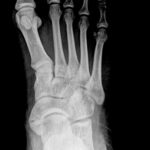

תסמונת עצם נביקולרית עודפת Accessory navicular syndrome

עצם נביקולרית נוספת קיימת מהלידה וקיימת בכ10 עד 15 אחוזים מהאוכלוסייה.

רק ב1% מהמקרים נגרמים סימפטומים ובמרבית האנשים עם עצם נביקולרית עודפת חיים חיים רגילים ולא מודעים לקיום העצם.